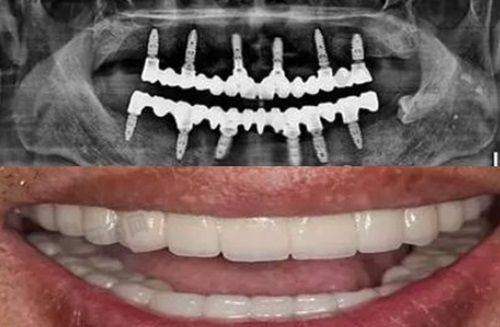

韩国奥齿泰种植牙是一种精良的口腔修复技术。它是通过外科手术的方式将人工牙根(种植体)植入缺牙区的牙槽骨内,经过一段时间(通常为3 - 6个月),使种植体与牙槽骨形成牢固的骨结合,然后安装基台、牙冠,从而修复牙齿的形态和功能。奥齿泰种植体采用了特殊的表面处理技术,能够促进种植体与牙槽骨的快速结合,提高种植成功几率。这种种植牙具有良好的生物相容性,能有效避免排异反应,为患者提供稳定、持久的牙齿修复成效。

精良的技术设备:医院引进了国内外精良的口腔诊疗设备,如口腔CT、数字化种植导板等。这些设备能够为医生提供正确的口腔数据,帮助医生更精细地进行种植手术。数字化种植导板技术可以在术前模拟种植过程,确定种植体的位置、角度和深度,大大提高了手术的安心性和成功几率。

患者到徐州夏禾口腔医院种植韩国奥齿泰种植牙,首先需要进行全方面的口腔检查和身体检查,包括口腔X光片、CT扫描等,以确定患者的口腔情况和身体状况是否适合种植牙。然后,医生会根据检查结果制定个性化的种植方案,并与患者沟通方案的具体内容和注意事项。接下来,患者需要进行种植手术,在局部麻醉下将种植体植入牙槽骨内。术后,患者需要按照医生的嘱咐进行护理,避免食用实力强、过烫的食物,保持口腔清洁。经过一段时间的愈合,种植体与牙槽骨形成骨结合后,患者需要再次到医院安装基台和牙冠,至此种植牙手术完成。